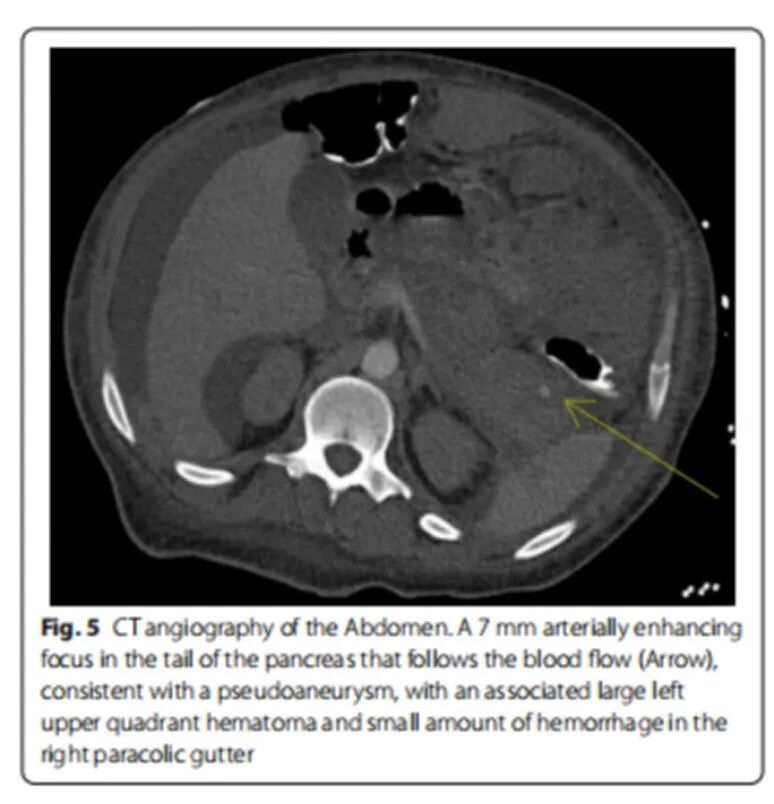

23岁青年男性,呼吸困难、胸痛伴咯血2周。既往G6PD缺乏病史及肥胖。吸食大麻。查体:BP 220/110 mmHg,心率120次/min,双肺听诊哮鸣音。实验室检查:肌酐升高2.03 mg/dl(179 μmol/l),微量蛋白尿。CRP 80 mg/L,ESR 67 mm/h。AN A 1:160阳性,RF、ANCA、补体、抗Sm抗体、抗组胺抗体均阴性。心脏彩超:EF 40%,左室肥厚,少量心包积液。胸部CT提示双侧小叶中心渗出,纵隔淋巴结肿大,心包积液。肾脏彩超及肾动脉彩超均无异常。外科胸腔镜右肺活检切除术,病理提示显微镜下多血管炎。泼尼松60 mg/d口服,症状无缓解,复查肺部CT示渗出加重。[Mollaeian A, et al. Auto Immun Highlights, 2021, 12(1):1.]

图片

6个月后出现高血压急症、心衰,心脏彩超示射血分数25%,心包积液。复查ANCA及相关免疫指标仍阴性。肾脏活检:肾小球硬化、毛细血管闭塞、管壁增厚。予激素及利妥昔单抗治疗。病情进展为透析依赖的终末期肾病,同时伴有胰腺炎、假性动脉瘤、腹膜后血肿、心包填塞。[Mollaeian A, et al. Auto Immun Highlights, 2021, 12(1):1.]